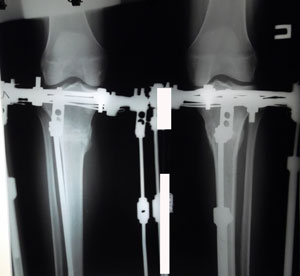

Дата операции 18.11.2014г.

У пациентки: двусторонняя ротация, плоскостопие тяжёлой степени.

Левая нога в норме, надколенник стоит прямо по центру.

С правым надколенником ещё работаем!